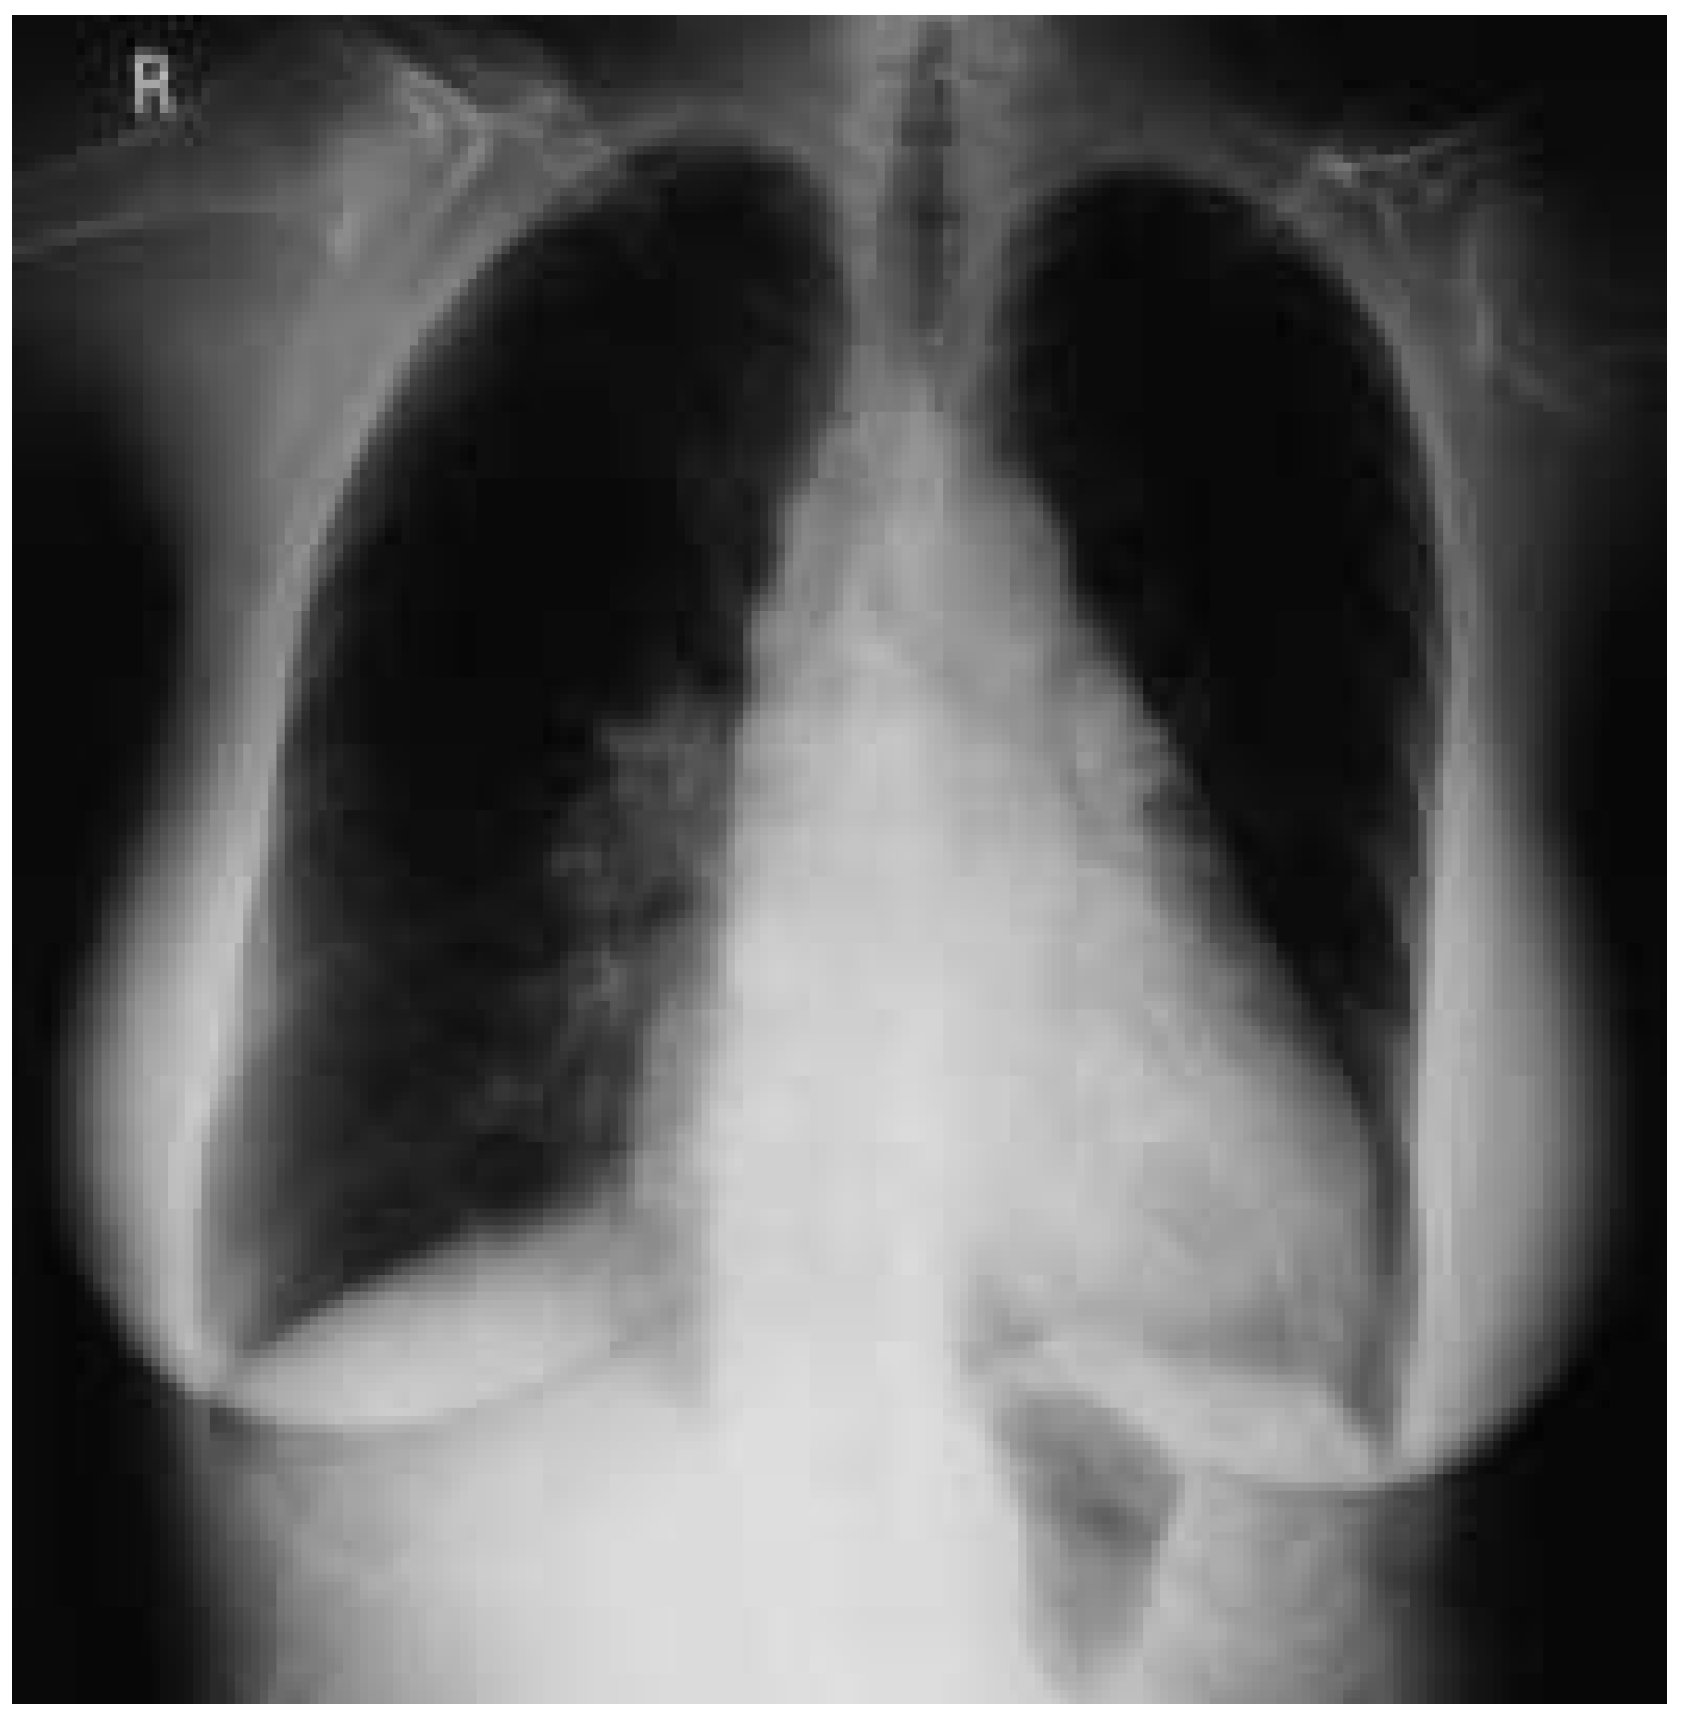

The chest-XR (Figure 2) shows cardiomegaly, some increased pulmonary vasculature and dilatation of the main pulmonary artery on the right side.

Figure 2. Chest X-ray with cardiomegaly and enlarged pulmonary artery on the right side.